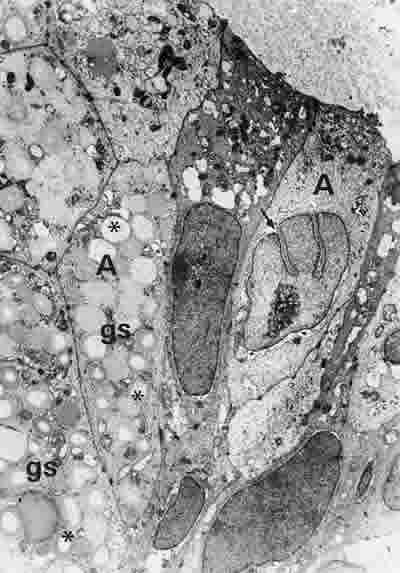

Figura 37

BIOPSIA EN UN PACIENTE CON SS1-GRADO II. LAS CÉLULAS ACINARES (A) SON GENERALMENTE MUY ALARGADAS. LA MAYORÍA DE ELLAS TIENEN POCOS ORGÁNULOS SUBCELULARES Y ESCASO NÚMERO DE GRÁNULOS DE SECRECIÓN (gs). EN OTRAS CÉLULAS ES FRECUENTE OBSERVAR GRÁNULOS DE SECRECIÓN CON EL CENTRO VACÍO (*). LOS NÚCLEOS SUELEN PRESENTAR INVAGINACIONES (FLECHA ARRIBA). MICROSCOPIA ELECTRÓNICA. MAGNIFICACIÓN ORIGINAL X3000.